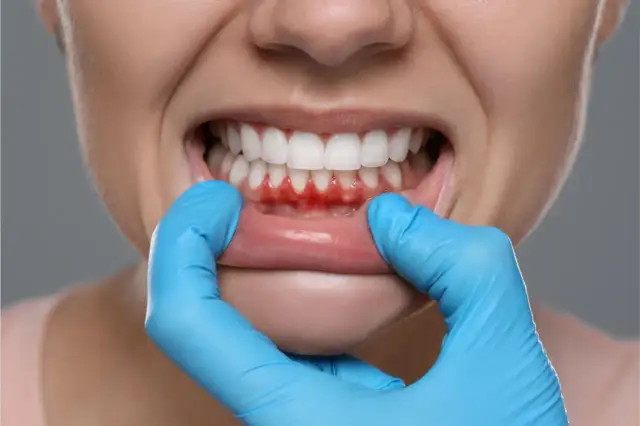

Cofające się dziąsła? Odbudowa, leczenie, profilaktyka i ceny

Cofające się dziąsła? Poznaj przyczyny, skuteczne domowe sposoby i profesjonalne metody leczenia, w tym przeszczepy. Sprawdź koszty i profilaktykę.